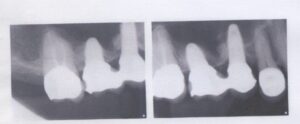

インプラント埋入直後

インプラント周囲炎

他院でのメンテナンスをされている方は当医院の歯周ポケット検査、

治療希望箇所が写っているレントゲン写真の撮影をお願いしております。